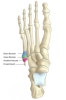

해부

1. 제1구역 : 발허리입방관절의 관절면 부위를 포함

2. 제2구역 : 넷째, 다섯째 중족골 뼈의 관절면을 포함(좀 더 오랜 기간 고정이 필요)

3. 제3구역 : 제2구역에서 원위쪽 부위로 1.5cm 부위까지(부정유합 또는 지연유합이 올 수도 있다.)